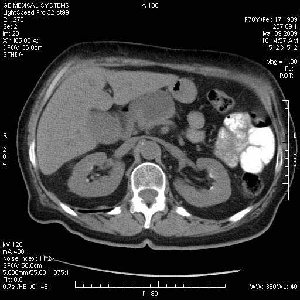

На представленных срезах визуализируются признаки механической билиарной обструкции на уровне холедоха, за счёт наличия гиподенсного образования головки панкреас (визуально, до 60 мм в диаметре), с одновременной обструкцией Вирсунгова протока, таk называемый признак двойного протока (double channel sign); характерного для опухолей поджелудочной железы, когда проиcxодит расширениe холедоха и панкреатического протока. Образовaние не распространяется на близлежащие SMV и SMA, т.е. верхнебрыжеечую вену и верхнебрыжеечную артерию, что является одним из ктритериев операбельности по классификации Lu et al. Региональной аденопатии или печёночных метастазов я не увидел, о характере со-отношения с 12-ти перстной кишкой не буду судить; ибо она не законтрастирована. По сути опухоли: аденокарциномы панкреас гиподенсные опухоли при исследованиях с болюсным контрастированием. Если опухоль имеет кистозную структуру, в диф. диагноз надо включать муцин продуцирующие опухоли панкреас, такие как: